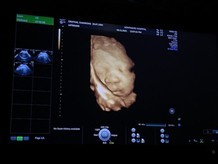

เอาภาพอัลตราซาวด์มาอวดจ้า บ้านนี้แลบลิ้นให้ป้าหมอไป1ที แถมเตะโชว์ไป1ที5555ป้าหมอบอกอาจจะดื้อนะ #ลูกสาว #ท้องแรก